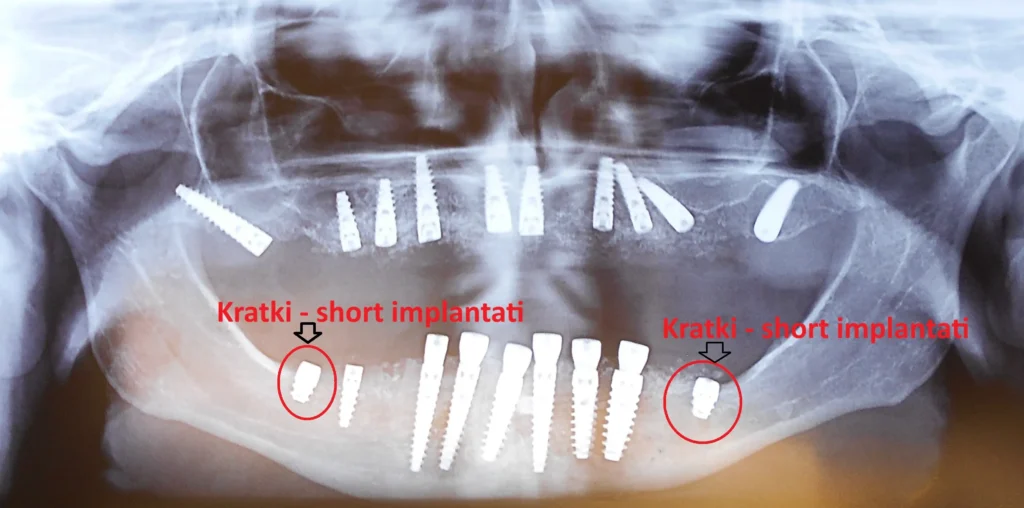

Short (kratki) implantati predstavljaju savremeno rešenje u implantologiji, koji se primenju kod pacijenta koji nemaju dovoljnu količinu kosti u bočnim regijama gornje i naorčito donje vilice, kako bi pružili podršku budućem protetskom radui i doprineli stabinosti i dugotrajnosti protetskog rada.

Za razliku od klasičnih implantata, koji su duži i zahtevaju veću količinu kosti, short implantati su kraći — ali zahvaljujući napretku u dizajnu i materijalima, jednako stabilni i dugotrajni

U situacijama kada u bočnim regijama vilice nema dovoljno koštanog tkiva za ugradnju standardnih implantata, rešenje mogu biti kratki (short) implantati. Ovi implantati predstavljaju savremeno i predvidivo rešenje koje omogućava ugradnju većeg broja implantata u oblastima ograničenog koštanog volumena, bez potrebe za dodatnim augmentacionim zahvatima(nadogradnjom kosti).

Cilj primene kratkih implantata je postizanje ravnomerne raspodele budućih sila žvakanja, čime se obezbeđuje veća stabilnost i dugotrajnost celokupnog protetskog rada kao i ugrađenih implantata. U kombinaciji sa standardnim implantatima, kratki implantati doprinose optimalnom funkcionalnom i estetskom rezultatu.

Short implantati najširu primenu imaju kod pacijenata sa smanjenom visinom kosti u donjoj i gornjoj vilici.

Važno je naglasiti da se kratki implantati nikada ne ugrađuju samostalno, već isključivo kao dopuna standardnim implantatima radi poboljšanja ukupne stabilnosti i biomehaničke ravnoteže sistema. Cena kratkih implantata ista je kao i cena standardnih implantata, jer se u oba slučaja koriste visokokvalitetni materijali i identične hirurške i protetske procedure.